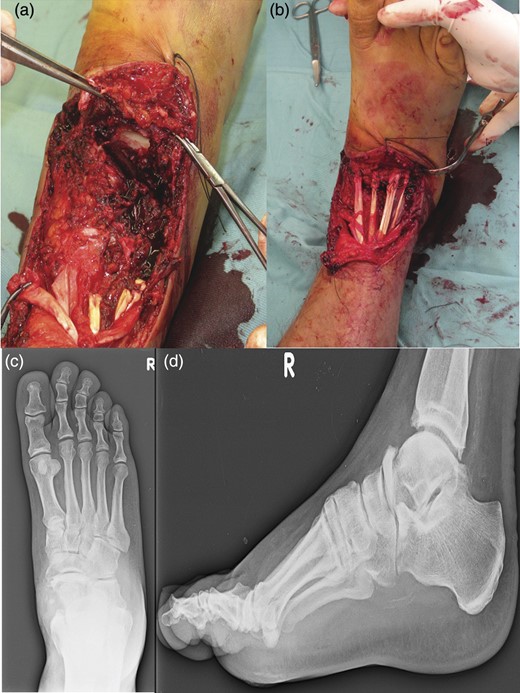

In August 2012, a 49-year-old-man presented to our hospital with a traumatic forefoot subamputation after a work accident. The trauma caused a lacerated wound in correspondence of the dorsal surface of the right foot. Radiographs and computed tomography (CT) examination confirmed the diagnosis of the loss of talus head during the trauma (Fig. 1).

AP (a) and lateral (b) radiographs and CT images (c, d) confirm the diagnosis of the loss of talus head during the trauma.

The patient underwent a first-time surgical repair. Abundant washing of the lacerated wound with saline solution and chlorhexidine was done. Injuries of dorsalis pedis artery, tibialis anterior tendon, estensor digitorum longus tendons, peroneus tertium tendon were revealed, with the loss of talus head and with a complex lesion of the talonavicular ligament. Tendinous structures damaged were surgically sutured and subsequently an antibiotic-loaded cement spacer was positioned into the bone gap to re-establish the joint congruence. The foot was put in a cast and kept non-weight bearing for 8 weeks (Fig. 2).

An image of the foot before the first-time surgical repair reveals the injuries of dorsalis pedis artery, tibialis anterior tendon, estensor digitorum longus tendons, peroneus tertium tendon, with the loss of talus head and with a complex lesion of the talonavicular ligament. (a) Tendinous structures damaged were surgically sutured and subsequently an antibiotic-loaded cement spacer was positioned into the bone gap to reestablish the joint congruence (b). AP (c) and lateral (d) radiographs of the foot in the cast after the surgical time.